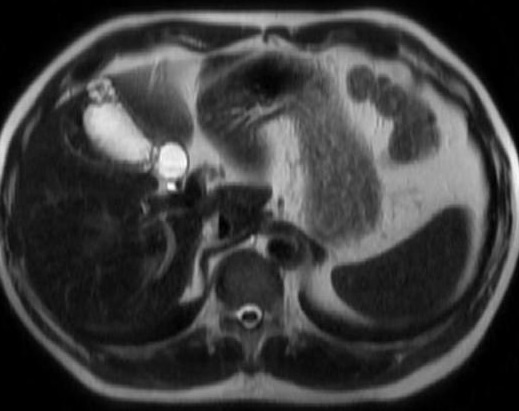

Image IRM de polyp

de la versicule biliaire est : Sur les coupe IRM ponderee

sur T2 aspect radiologique en nodulaire ou en bourgeonaise

a hypointense au milieu de la vesicule biliaire avec sa

contenue tres hyperintense ( l'eau est hypersignal )

Image de deux polyp

vesiculaire en aspect polypoide a hypointense situe

a infundibulum et au fond de la vesicule biliaire .

La vesicule biliare et sa contenue est tres intense

, voie biliaire intrahepatique et une partie de VBP

est en se voyant . Image radiologique IRM en coupe

coronal ponderee sur T2 |

Une autre cas de polyp vesiculaire :

image polypoide a hypointense situe au fond de la

vesicule biliaire . La vesicule biliaire et sa

contenue est tres hypersignal : Image

radiologique IRM ponderee sur T2 et en coupe

sagitale |